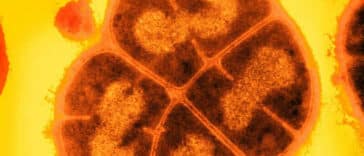

Alors que l’humanité s’adapte à des défis majeurs tels que les pandémies, les crises climatiques et les progrès rapides de l’intelligence artificielle, une nouvelle menace pourrait surgir d’un domaine encore peu exploré : celui des « formes de vie miroir ». Un collectif de 40 scientifiques de renommée internationale alerte sur les risques posés par … Lire la suite de Menace invisible, des dizaines de scientifiques alertent sur les « formes de vie miroir » More